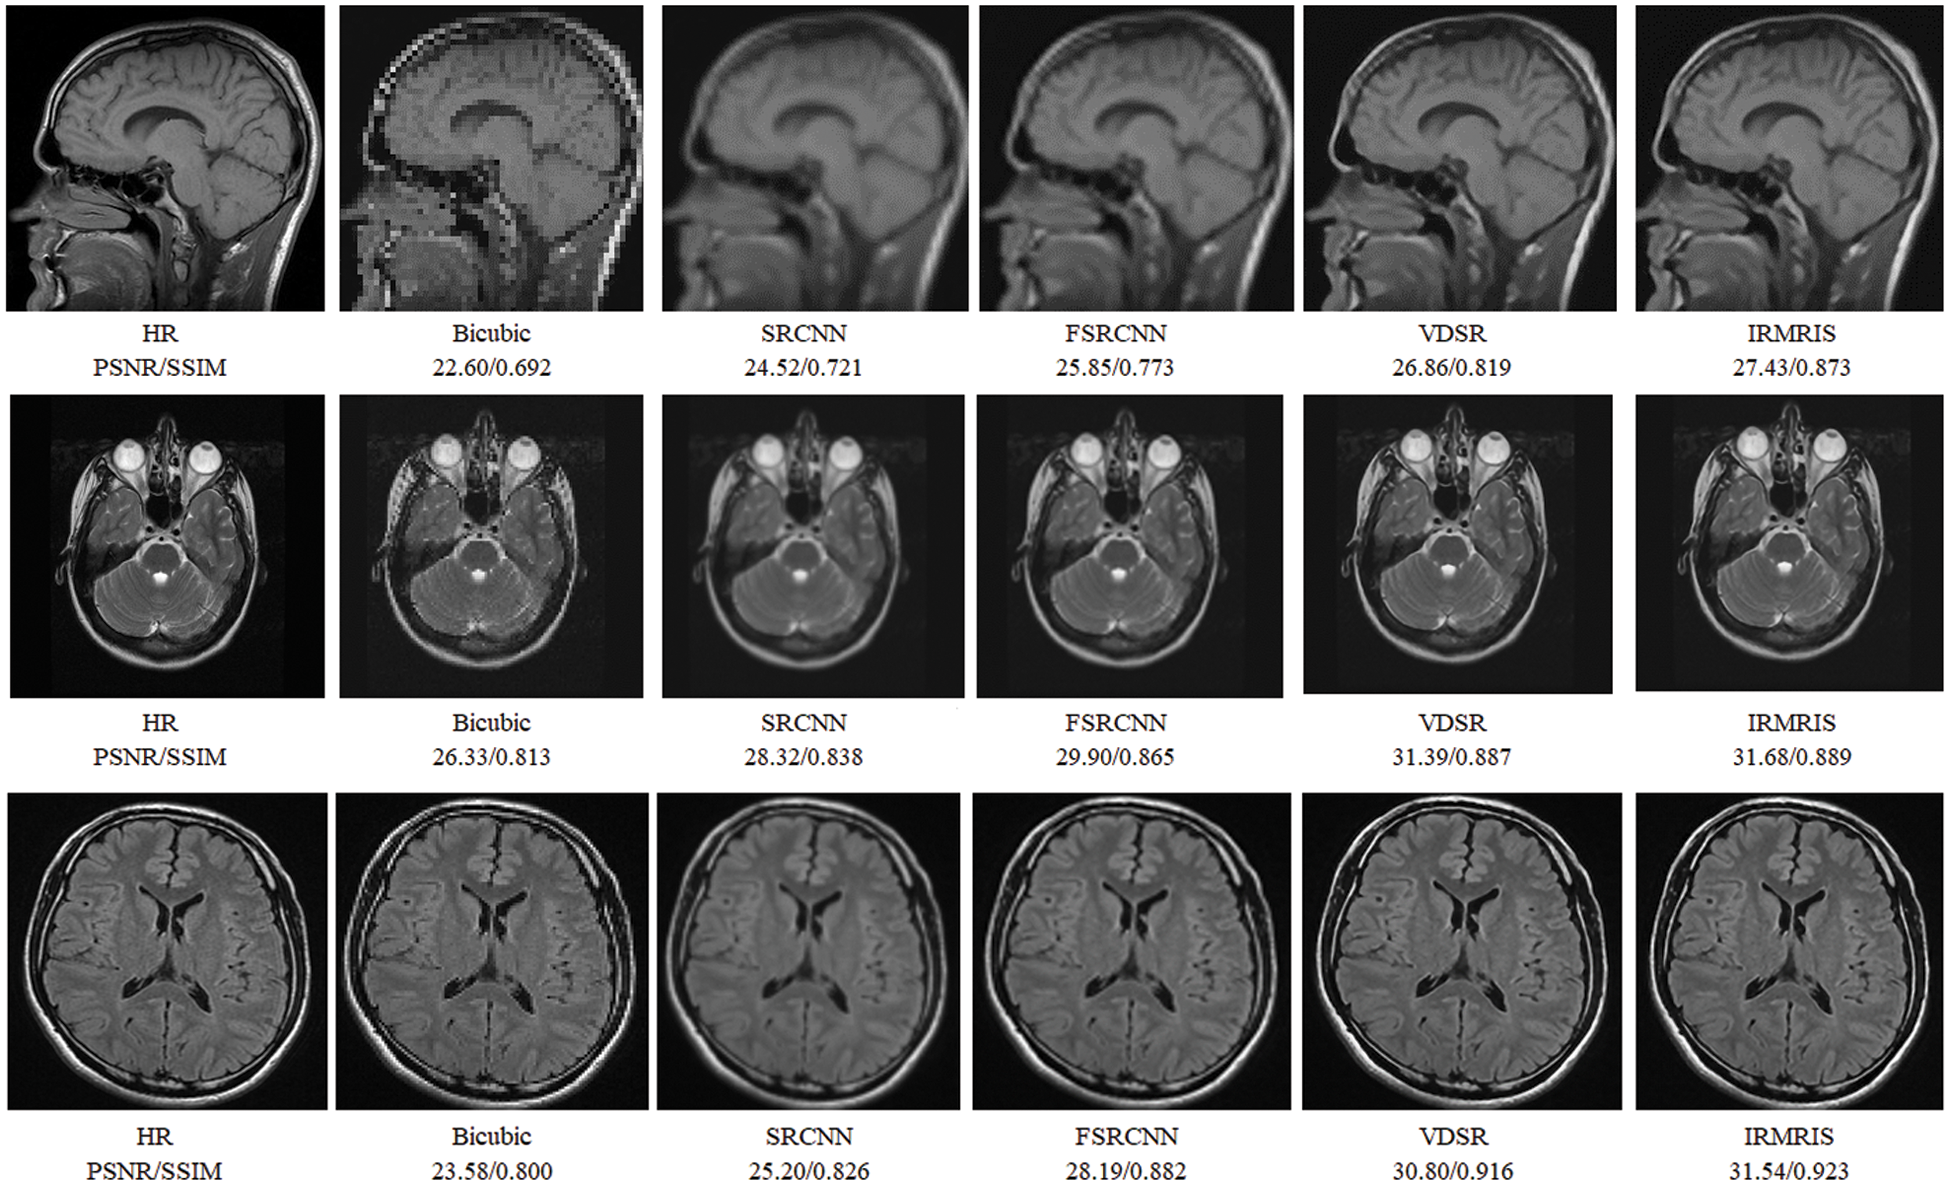

To evaluate the comparison quality of image SR methods with the proposed approach, particularly Bicubic, A+, SelfExSR, RFL, SRCNN, FSRCNN, VDSR, DRCN, LapSRN, DRRN, and IDN techniques. Table 2 presents the quantitative results of different algorithms on the Set5, Set14, BSDS100, and Urban100 test data sets, with an enlargement factor of 2×, 3×, and 4× accordingly. Fig. 6 shows the quantitative performance of state-of-the-art approaches in terms of PSNR vs. network parameters. Our proposed model (IRMRIS) has fewer parameters than the VDSR, DRCN, and LapSRN. Despite having a lower footprint as compared to CNN-based approaches, the performance of the proposed model was demonstrated to be state-of-the-art. As compared to the Bicubic, A+, SelfExSR, RFL, SRCNN, FSRCNN, VDSR, DRCN, and LapSRN. Furthermore, our IRMRIS model has about 1.87, 0.78, 0.79, 0.86, 0.67, 0.56, 0.56, 0.29, and 0.27 dB improvement on the BSDS100 dataset for enlargement factor 3× image SR. Figs. 7–10 present a visual performance comparison of the brain MRI images at enlargement factor 4× SR. The result of the baseline method (bicubic) and SRCNN clearly shows blurry MRI image, but our proposed IRMRIS reconstruct the best results as compared to another state-of-the-art methods MRI image SR.

Figure 7: Perceptual quality comparison of our method with other deep learning-based methods using MRI images at 4× super-resolution